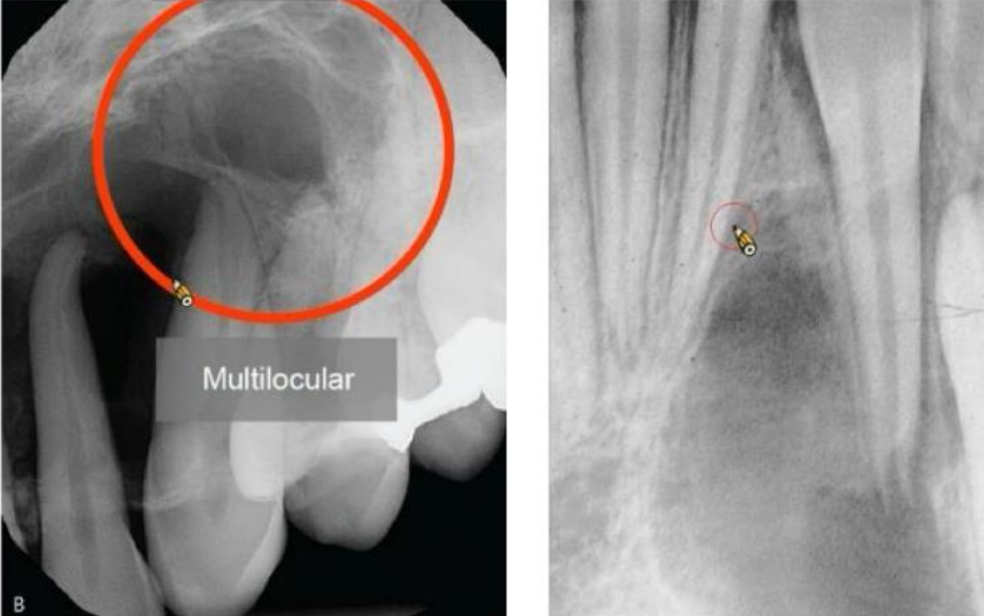

Ameloblastoma 多囊腫型 (coventional solid or multicystic intraosseous)

下顎 (80-85%) -

• 最常見(80%),長得慢,通常會到了腫瘤很大時才來就診。

• 頰舌擴張

• 牙根吸收

• 局部侵犯,少轉移,預後好

單一囊腫型(unicystic) 下顎後 ~23y

• 預後較多囊好

• 常圍繞未萌發的牙齒,特別是第三大臼齒